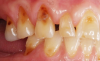

The BEWE is a scoring system that evaluates the most severely affected surface in each sextant, recording one of the four-level scores as follows30: 0 = no erosive tooth wear (Figure 8); 1 = initial loss of surface texture (Figure 9); 2 = distinct defect, hard-tissue loss <50% of surface area (Figure 10); 3 = hard-tissue loss ≥50% of surface area (Figure 11). (Scores 2 and 3 often involve dentin.) After all sextants are assessed, the sum of scores provides the risk level of each patient and may help guide the design of a professional management program for the patient.

Fig 8. BEWE scoring system: score 0 = no erosive tooth wear (Fig 8); score 1 = initial loss of surface texture (Fig 9); score 2 = distinct defect, hard-tissue loss <50% of surface area (Fig 10); score 3 = hard-tissue loss ≥50% of surface area (Fig 11)

Fig 9. BEWE scoring system: score 0 = no erosive tooth wear (Fig 8); score 1 = initial loss of surface texture (Fig 9); score 2 = distinct defect, hard-tissue loss <50% of surface area (Fig 10); score 3 = hard-tissue loss ≥50% of surface area (Fig 11)

Fig 10. BEWE scoring system: score 0 = no erosive tooth wear (Fig 8); score 1 = initial loss of surface texture (Fig 9); score 2 = distinct defect, hard-tissue loss <50% of surface area (Fig 10); score 3 = hard-tissue loss ≥50% of surface area (Fig 11)

Fig 11. BEWE scoring system: score 0 = no erosive tooth wear (Fig 8); score 1 = initial loss of surface texture (Fig 9); score 2 = distinct defect, hard-tissue loss <50% of surface area (Fig 10); score 3 = hard-tissue loss ≥50% of surface area (Fig 11)